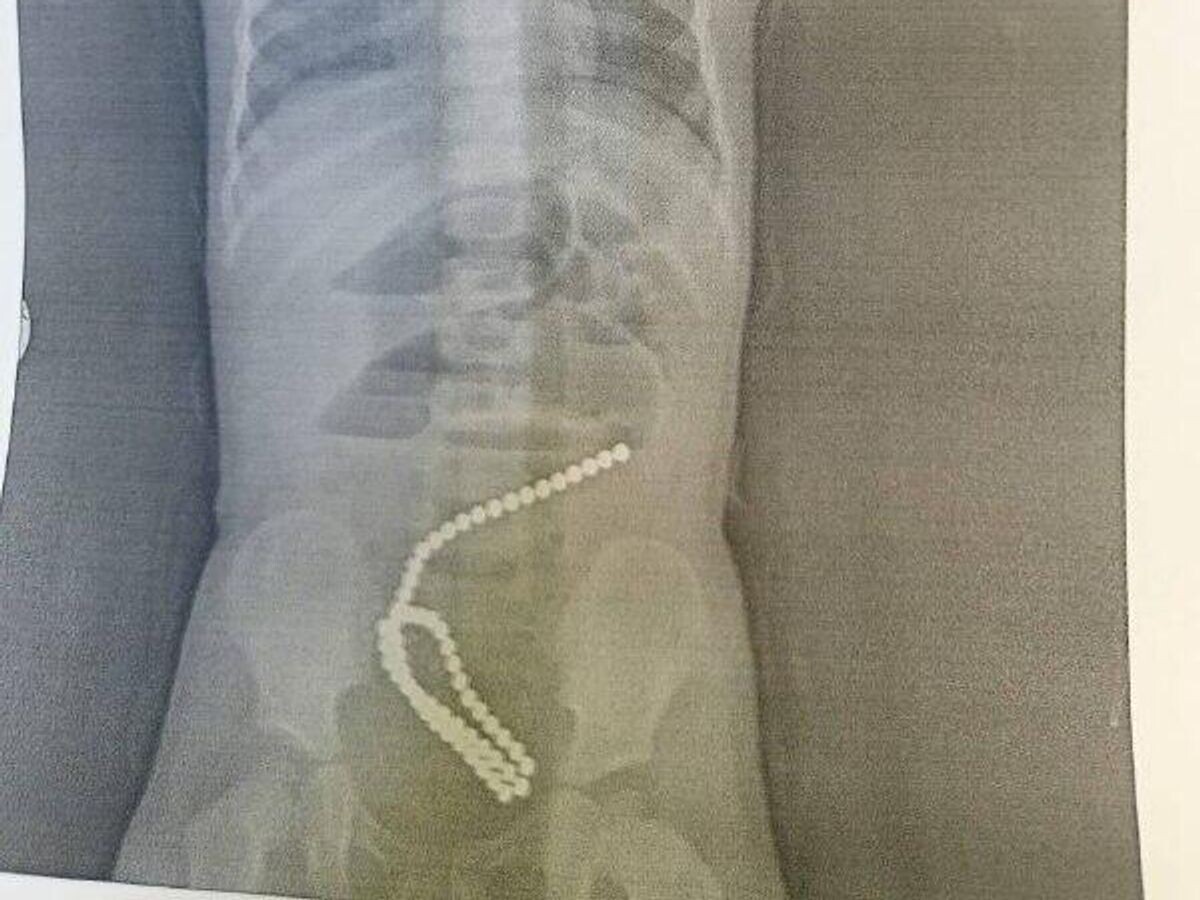

Детские хирурги Городской больницы № 7 Комсомольска-на-Амуре спасли ребенка, проглотившего магниты© Фото : Министерство здравоохранения Хабаровского края

"Детские хирурги городской больницы № 7 Комсомольска-на-Амуре спасли ребенка, проглотившего магниты <...>. При диагностическом обследовании были обнаружены инородные тела в кишечнике — 60 маленьких магнитов-шариков (такие элементы входят в наборы развивающих игрушек)", — говорится в релизе.

По данным заведующего детским хирургическим отделением, врача-детского хирурга высшей квалификационной категории Андрея Костенко, проглотить несколько магнитов — крайне опасно, они могут сгруппироваться в желудочно-кишечном тракте и сдавить стенку кишечника, что может привести к некрозу, перфорации, закупорке кишечника, образованию свищей, завороту кишечника. У пострадавшей девочки инородные тела вызвали кишечную непроходимость, повреждение стенок кишечника.